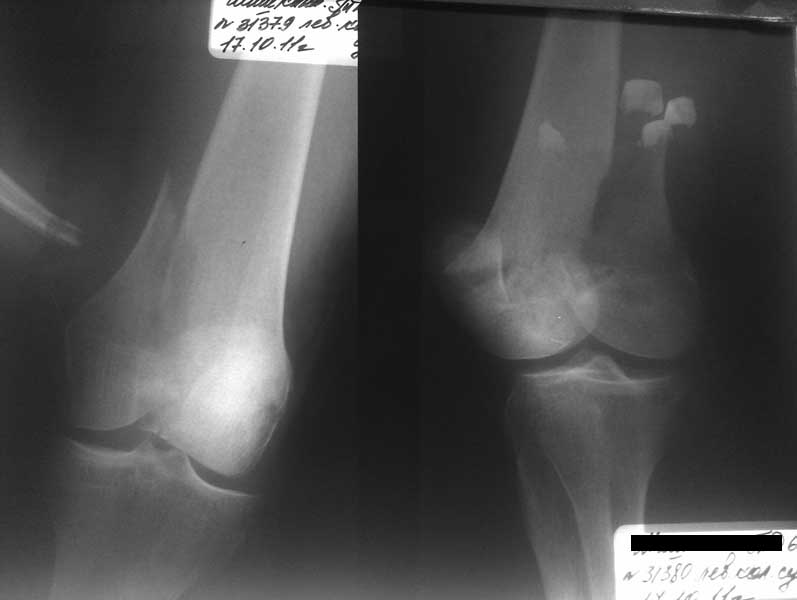

Представленный снимок не дает полную информацию. Там вроде простой перелом, но на самом деле, кроме смещенного (латерального, возможно медиального?) мыщелка на второй проекции имеется медиальный короткий дистальный фрагмент в флексии. Надо было сделать прямой снимок с захватом малоберцовой, который ориентировал бы стороны. Без КТ обычный снимок в дистракции поможет разобраться в топографии фрагментов.

Во время фиксации надо соблюдать осторожность, особенно с коротким фрагментом на другой стороне. Обычно на прямой проекции трудно заметить флексионную деформацию мыщелка и упускается адекватная фиксация. Без пластины винты не смогут удержать, и мыщелок на второй стороне может сместиться. Для фиксации надо развернуть мыщелок и удержать винтами. Качество межмыщелковой репозиции надо проконтролировать артротомией. Из всех доступов только передне-латеральный доступ (Swashbuckler) даст обзор для ревизии качества фиксации, который в будущем может быть использован для артропластики.

Кстати, из вашего снимка, если отмечены вашим рентгенологом правильно, тогда получается снимок левого колена, и, соответственно, длинный переходящий в диафиз мыщелковый фрагмент находится медиально. Если так, тогда меняется сценарий фиксации!!!

Сразу не обратил ваше внимание именно на это, что сломаны оба мыщелка, и больший является именно медиальным мыщелком, а пластины ставятся по латеральной стороне, соответственно, в этом медиальном мыщелке от пластины останутся только концы винтов, которые не обеспечат достаточной фиксации мыщелка.

И не обратите, коллега, пока не сделаете четкие анфасные снимки (лучше с дистракцией) где будет четко визуализироваться малоберцовая кость. Думается, что и КТ здесь будет уместно, дабы не пропустить возможное флексионное повреждение (перелом Hoffa).

Коллеги, извиняюсь за задержку с результатом. Через медиальную артротомию обнажили н/3 бедра, отрепонировали внутренний мыщелок, затем по нему сопоставили суставную поверхность бедра с латеральным мыщелком.

Больная выписана в ортезе с регулируемым углом сгибания в колене, с рекомендациями через 3 нед. удалить спицы и начать разрабатывать сустав.

По прямому снимку репозиция удалось, поздравляю! А с латеральной стороны подозрение на флексионный компонент латерального мыщелка остается, а снимок получился косым, надо было бы повторить.